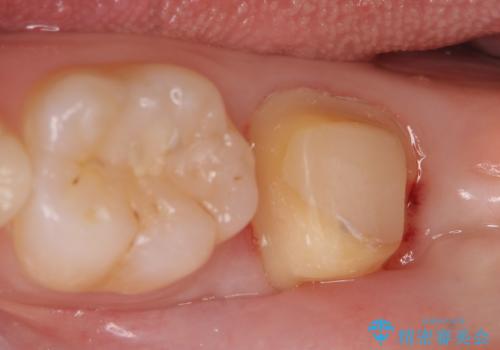

左下7遠心(下記のX線写真の左側)の歯質が歯肉縁下でかつポケットも深かったため、歯茎を下げる歯周外科を行いました。

その後歯茎の治りを待ちポケットが正常値であることを確認後、オールセラミッククラウンによる補綴を行いました。